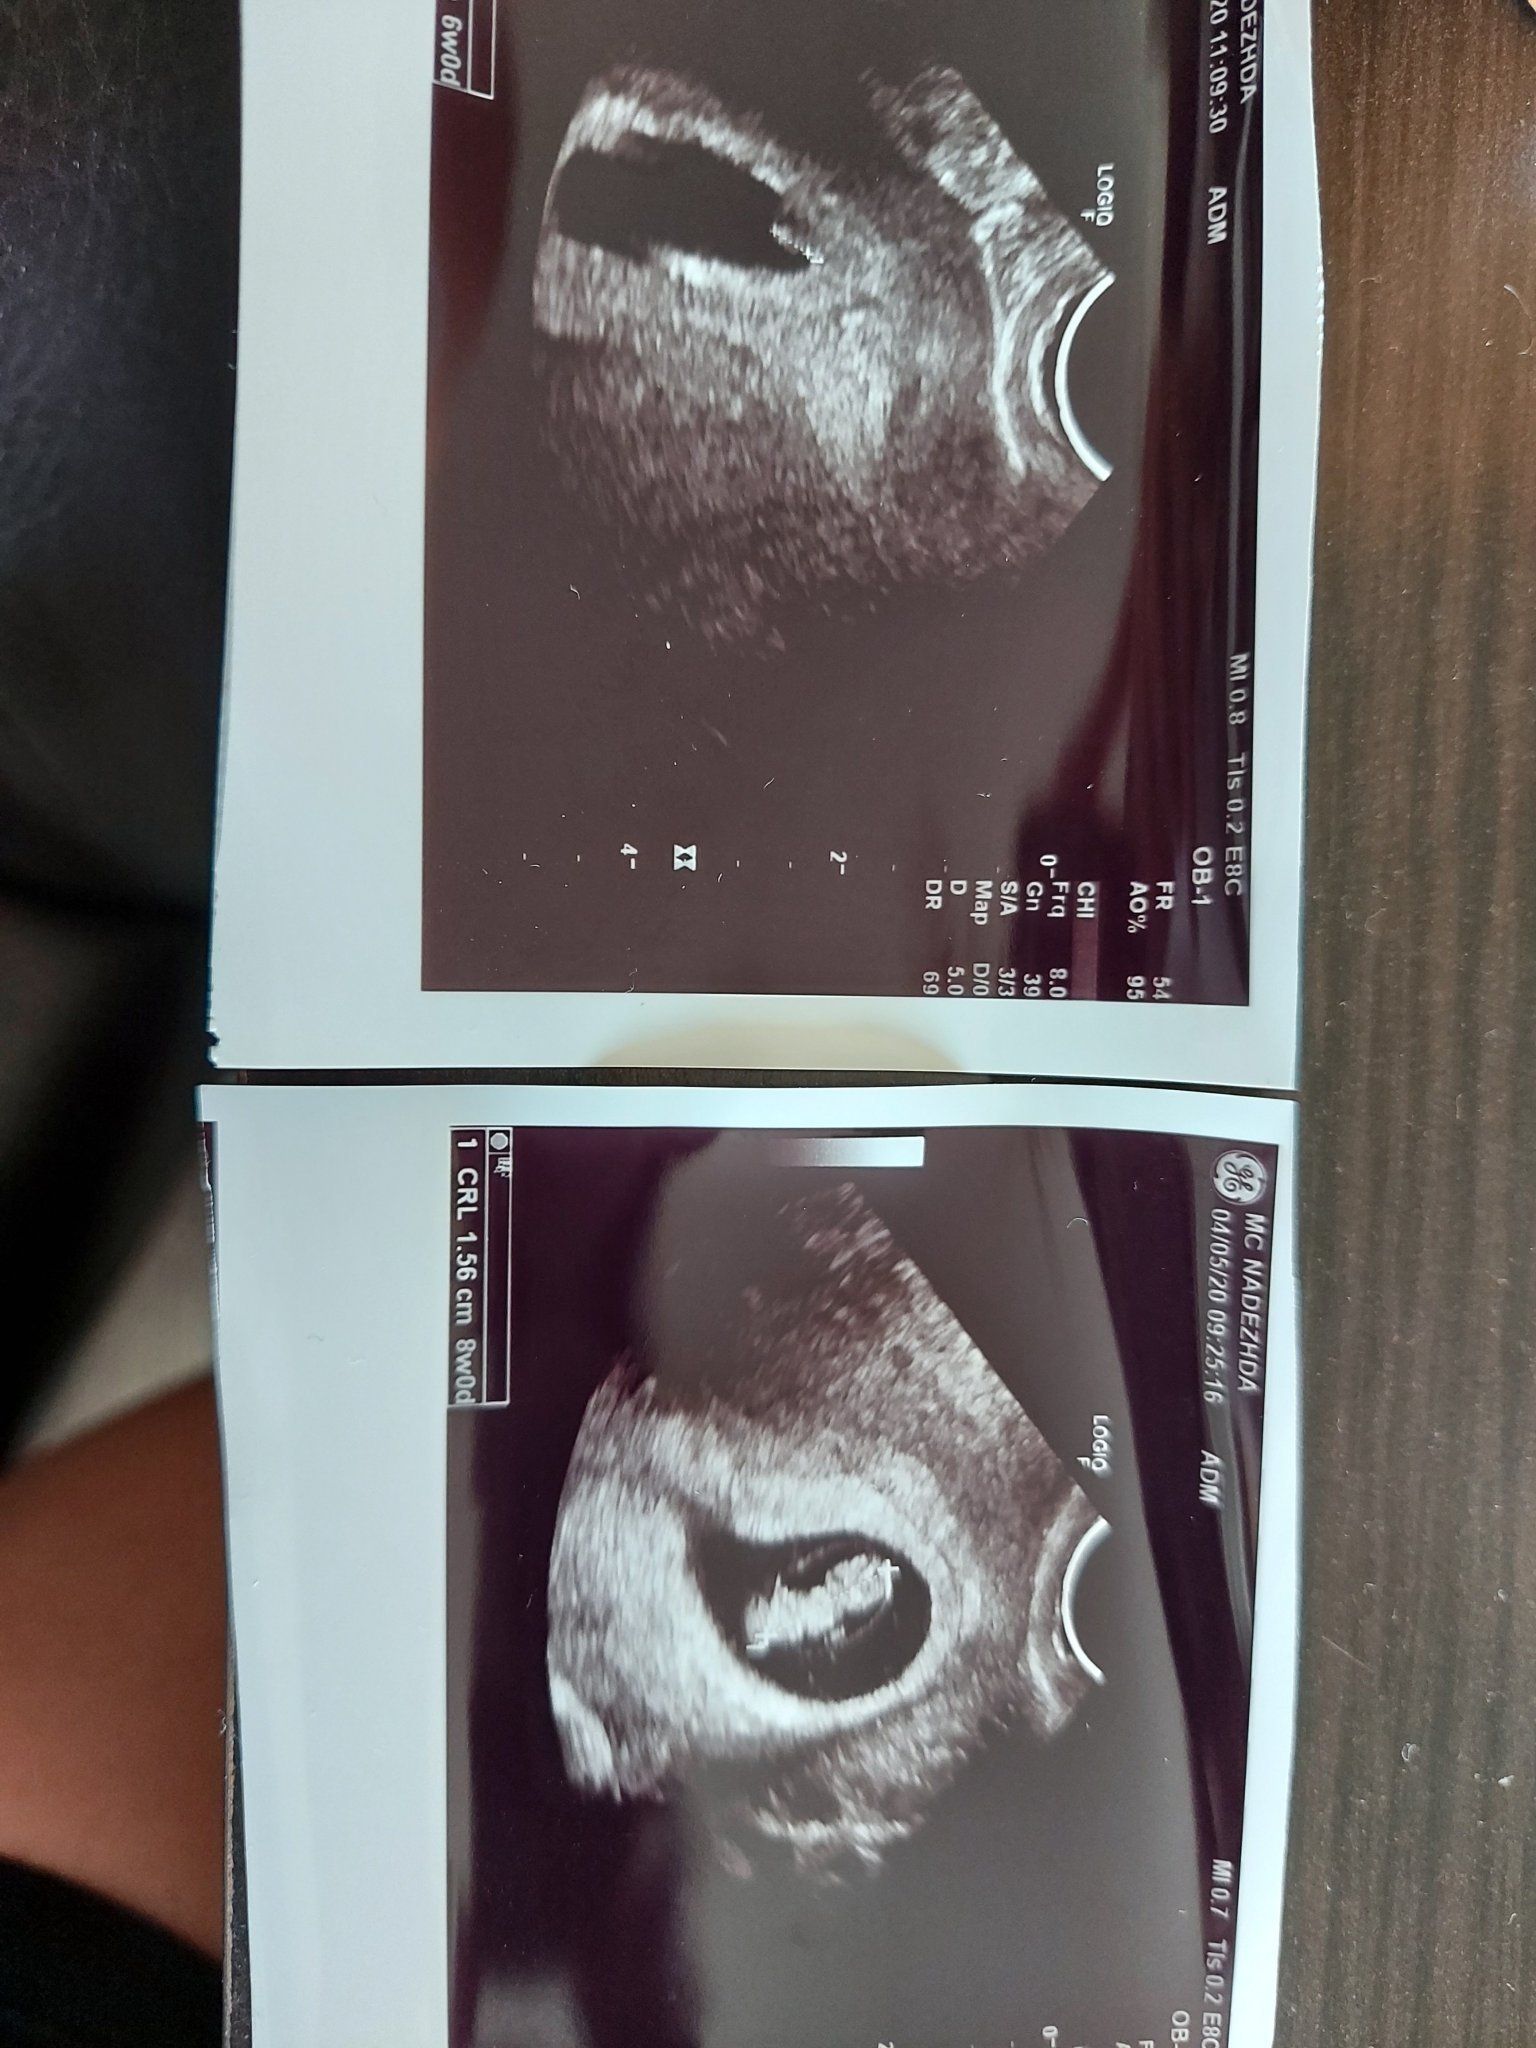

Кога се прави ранната фетална морфология?

Кога трябва да е следващият преглед след 6 седмици и 4 дни?